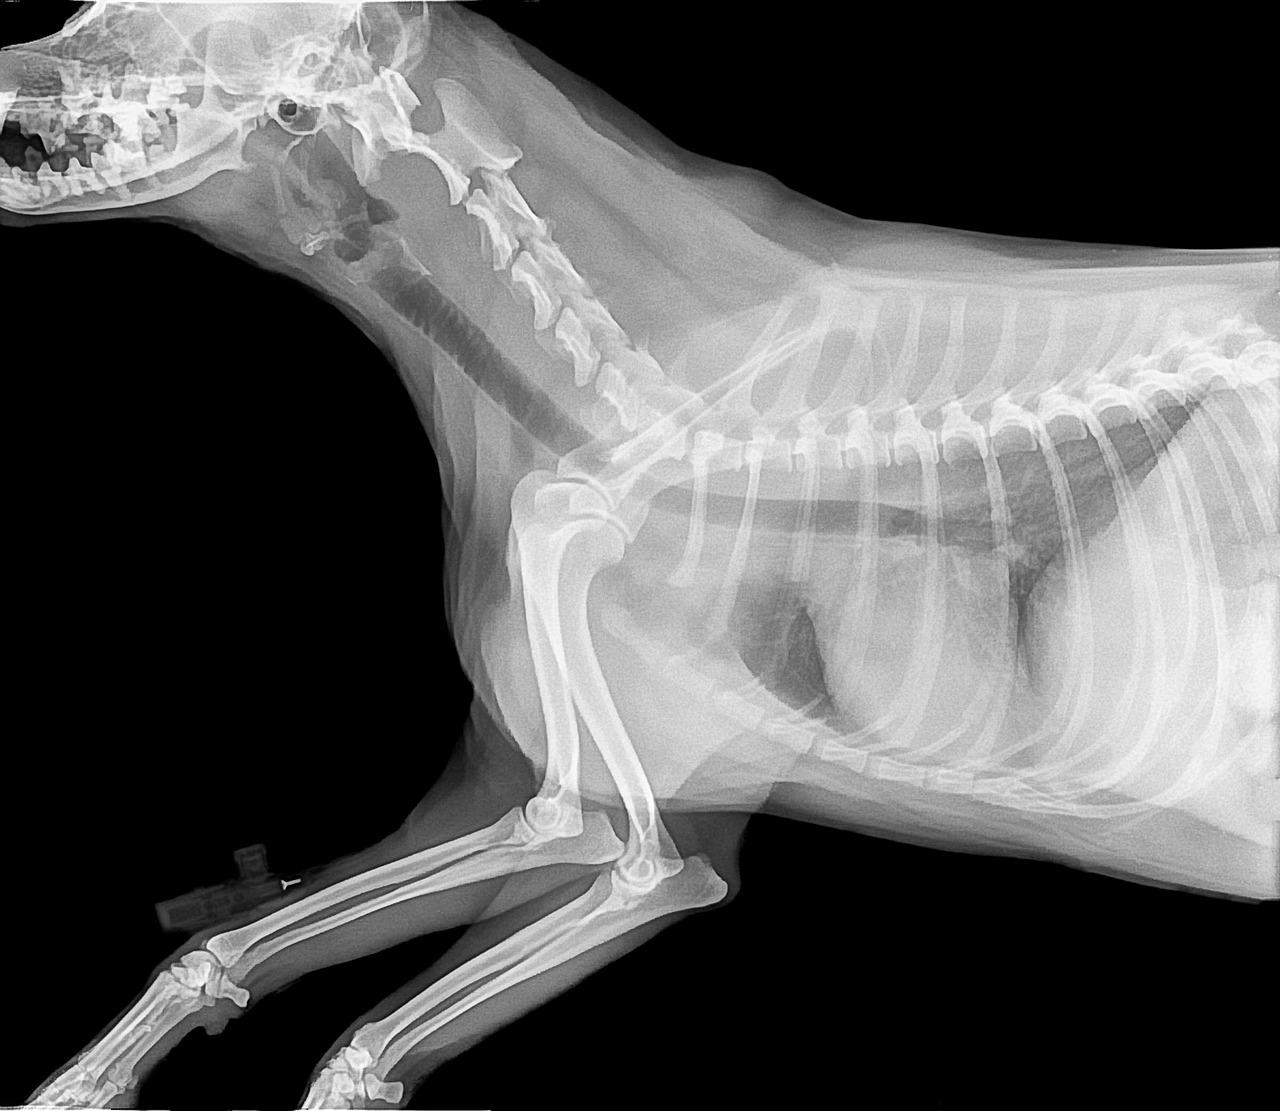

La radiografia en mascotas nos permiten conocer el estado de los huesos, tejidos, organos internos, con lo cual podemos prevenir enfermedades o descartar fracturas en tu mascota.